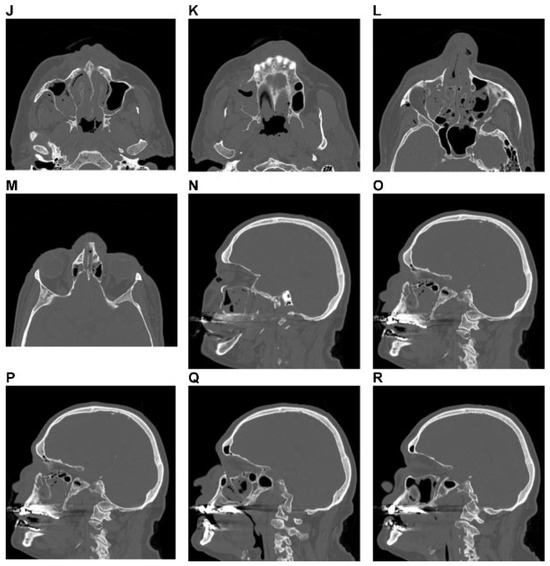

Figure 7.

Zygoma Fracture left with dorsocranial displacement and antral impaction. Three-dimensional (3D) computed tomographic (CT) scans—(A) frontal view, (B) caudofrontal view, (C) oblique lateral view left, (D) caudolateral view; panoramic X-ray—(E) OPT. (F–I) coronal CT scans; (J-M) axial CT scans: sagittal CT scans—(N) next to medial orbit wall left, (O) at the level of medial orbital floor left, (P) just medial to inferior orbital fissure left. (Q) Level 3 Code : 92 m.Oil.I1.Z0i - 93 m.M0, Orbit (left)R(li).W1(li)2(li). This case example CMTR-92-102 is made available electronically for viewing using the AOCOIAC software at www.aocmf.org/classification. Narrative description: Zygoma fracture left. Details: fracture following ZFS, fragmentation along ZSS with intermediate fracture extending into the greater wing of sphenoid and the orbital flange of the zygoma, single fracture-infraorbital process, multifragmentation of facial antral wall left, ZMC and tuber region (LCM), zygomatic arch fracture. Dentition (FDI): Lack of 18–15; 26–28. Maxillary alveolar process atrophy: severe displacement: cranial and dorsal displacement (translational), antral impaction (rotation around sagittal axis through zygomatic body). Internal orbit left: Involvement confined to anterior orbital section and midorbit—anterolateral inferior and lateral fragments in juxtaposition to inferior orbital fissure.

Figure 9.

Naso-orbito-ethmoidal fracture (Example 2)—NOE extreme Type III bilateral. Imaging: Three-dimensional (3D) computed tomographic scans (A) frontal view, (B) oblique lateral view right, and (C) oblique lateral view left. Narrative description: Medium-/small-sized fragments and extreme displacement (loss of interfragmentary contact) in a bilateral Naso Orbito Ethmoid Fracture in combination with a Le Fort I, II fracture, and left zyogma fracture. (D) Level 3 Code: 92 Z1i.I1i.L1.Pt0.Oim.U1m.Omil.Pt0.L1.I1i.Z1li - 93 m.M - 94 F1.m.F1m, Orbit (right): R(im).W1(im)2(im), Orbit (left): R(lim).W1(lim)2(lim). This case example CMTR-92-105 is made available electronically for viewing using the AOCOIAC software at www.aocmf.org/classification. Note: Involvement of midface and craniofacial transition as a consequence of fractures extending into the superomedial quadrants of the orbital rim - this is indicated by the marking of the entire frontal bone area.